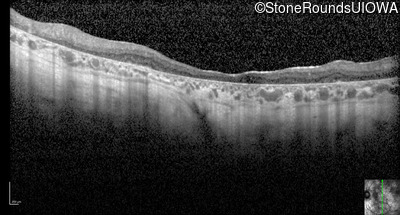

Optical Coherence Tomography - Left - 10/225

Exemplar / OCT Stack